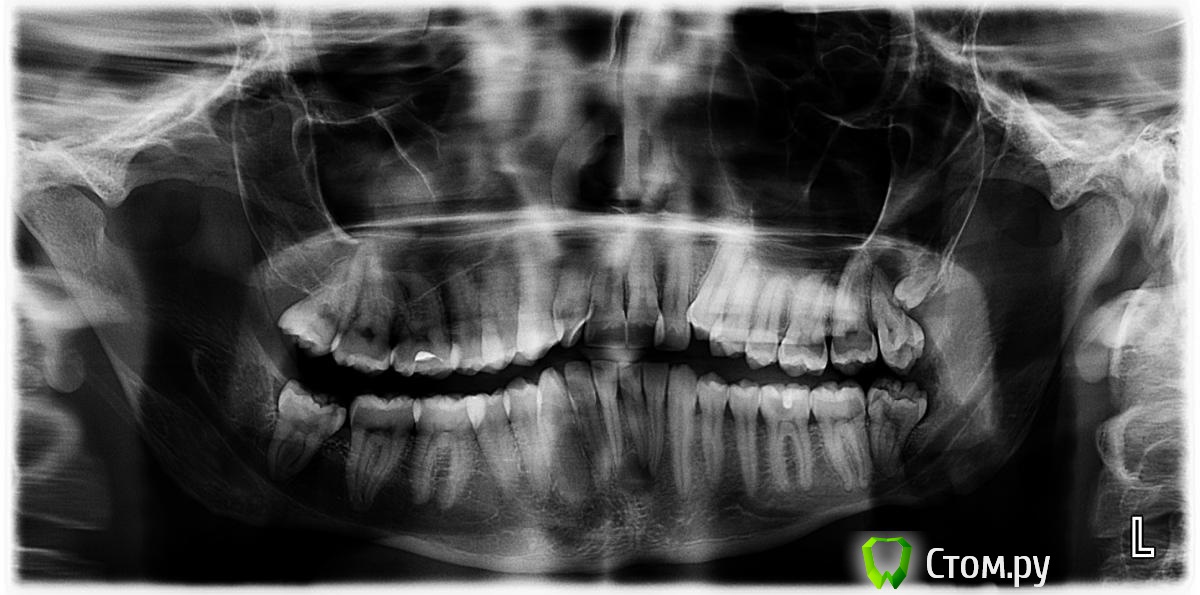

Afffinity Опубликовано 17 марта, 2014 Поделиться Опубликовано 17 марта, 2014 1. Обратился мужчина, 25 лет, с жалобами на боли от холодного и горячего в области 36 зуба. На жевательной поверхности как таковой кариозной полости не было. Осталась полость от выпавшей пломбы. Когда выпала не уточнял, но зуб беспокоил 3й день. Как говориться, пипец один не приходит, а рядом с собой везет маленькую тележку. Сделали панорамник:Помимо эндо 36 было еще и эндо 31. Благо пациент разумный был. конечный результат тутИнструментация М-ту до 30/05. Ирригация гипохлорит, вода, ЭДТА, гипохлорит, сушка. Пломбирование вертикалка(Аппарат от Сиброн эндо, скажу не очень убобный. Бифилл лучше). Востановление композитный билдап. Апикальная часть обработана до 40/04 (дентин был мягкий, поэтому и расширять пришлось как следует). В ближайшее время будем вызванивать на реколл. Ссылка на комментарий

шахтер Опубликовано 17 марта, 2014 Поделиться Опубликовано 17 марта, 2014 1. Обратился мужчина, 25 лет, с жалобами на боли от холодного и горячего в области 36 зуба. На жевательной поверхности как таковой кариозной полости не было. Осталась полость от выпавшей пломбы. Когда выпала не уточнял, но зуб беспокоил 3й день. Как говориться, пипец один не приходит, а рядом с собой везет маленькую тележку. Сделали панорамник:Астафьев панорам..jpgПомимо эндо 36 было еще и эндо 31. Благо пациент разумный был. конечный результат тутR1.jpgИнструментация М-ту до 30/05. Ирригация гипохлорит, вода, ЭДТА, гипохлорит, сушка. Пломбирование вертикалка(Аппарат от Сиброн эндо, скажу не очень убобный. Бифилл лучше). Востановление композитный билдап. R3.jpgАпикальная часть обработана до 40/04 (дентин был мягкий, поэтому и расширять пришлось как следует). В ближайшее время будем вызванивать на реколл. А что 26,27,28,37? Снимок мало информативен . Нужна кт . Ссылка на комментарий

Л Ю С Я Опубликовано 17 марта, 2014 Поделиться Опубликовано 17 марта, 2014 В 3.1 была кар полость? На какой поверхности? По оптг непонятно Ссылка на комментарий

Afffinity Опубликовано 17 марта, 2014 Автор Поделиться Опубликовано 17 марта, 2014 А что 26,27,28,37? Снимок мало информативен . Нужна кт . Пациент пропал)В 3.1 была кар полость? На какой поверхности? По оптг непонятноБыла, на дистальной поверхности. Ссылка на комментарий